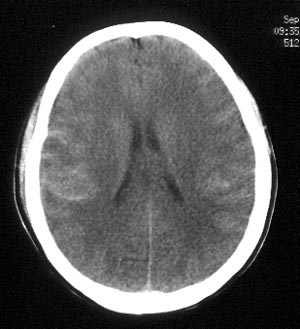

女性,36岁。头部外伤半小时,现觉头痛,有呕吐,无昏迷。

ct平扫:双侧脑沟、脑裂见密度增高,双侧大脑半球及颅后窝脑实质未见异常密度改变。

ct诊断:蛛网膜下腔出血。